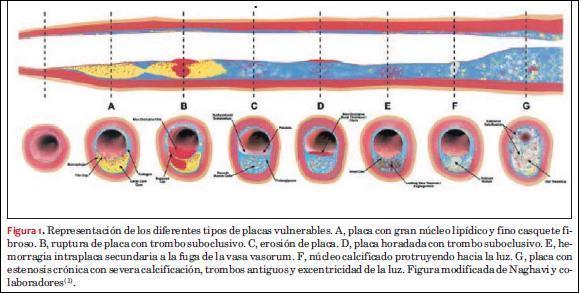

El término placa vulnerable se ha usado en la literatura médica con diferente significado(1,41). Actualmente se utiliza para definir aquellas placas de ateroma susceptibles a complicaciones, es decir, con elevada probabilidad de producir rápida progresión, presentar accidentes de placa (ruptura, fisura, erosión, nódulos calcificados), generar trombosis y convertirse en placas culpables de eventos cardiovasculares(1). Diferentes hallazgos anátomo-patológicos han sido identificados en una placa de ateroma como elementos de mayor vulnerabilidad. Se destacan, entre ellos, la rotura de placa con o sin trombo sobreimpuesto, la presencia de un casquete fibroso fino con un gran core lipídico, hemorragia intraplaca, un gran infiltrado inflamatorio activo o la estenosis crítica de la luz arterial por la extensión crónica de una placa excéntrica(23,42). En la figura 1 se observa la representación esquemática clásica de la clasificación histopatológica de los diferentes tipos de placas vulnerables tomado de Naghavi y colaboradores(1).

Los mecanismos de ruptura de una placa de ateroma son complejos y dependen de características morfológicas y estructurales así como de factores biomecánicos de las placas de ateroma y de los sectores arteriales adyacentes(9-11). Un modelo biomecánico de la complicación de las placas de ateroma indicaría que tensiones de diferente dirección en la placa de ateroma y/o entre sectores arteriales adyacentes, producidas por cambios cíclicos de presión arterial a lo largo del tiempo, podrían determinar alteraciones parietales que promuevan accidentes de placa por “fatiga” biomecánica, que podría ser diferente en función de las propiedades de los materiales que componen la PAC y su entorno(11,43,44). Es aceptado, al respecto, que la ruptura de una placa de ateroma posiblemente ocurra cuando las fuerzas de carga excedan la resistencia del material de la PAC(43). El análisis de los mecanismos biomecánicos de la complicación de una placa de ateroma han sido mayoritariamente evaluado en la dirección circunferencial de la arteria (deformación radial)(44-46). Investigadores como Cheng y colaboradores demostraron que el valor de la tensión circunferencial máxima a la que estaban sometidas las placas de ateroma de pacientes sintomáticos superaba al triple de aquella registrada en placas de pacientes asintomáticos(47). Por otro lado, una placa con gran núcleo lipídico excéntrico, característica morfoestructural asociada a elevado riesgo, podría significar una desventaja mecánica al redistribuir la tensión circunferencial a la región del “hombro de la placa”(43). La tensión impuesta sobre las placas usualmente se concentra en dicho lugar(43), alcanzando valores máximos(48), y es donde la capa fibrosa es más fina y probablemente se erosione o fracture más fácilmente(43). Según un reporte de Richardson y colaboradores, aproximadamente en el 60% de los casos, esta es el área en donde la capa fibrosa tiende a romperse, si bien el sitio preciso depende de la configuración de la placa de ateroma(45).